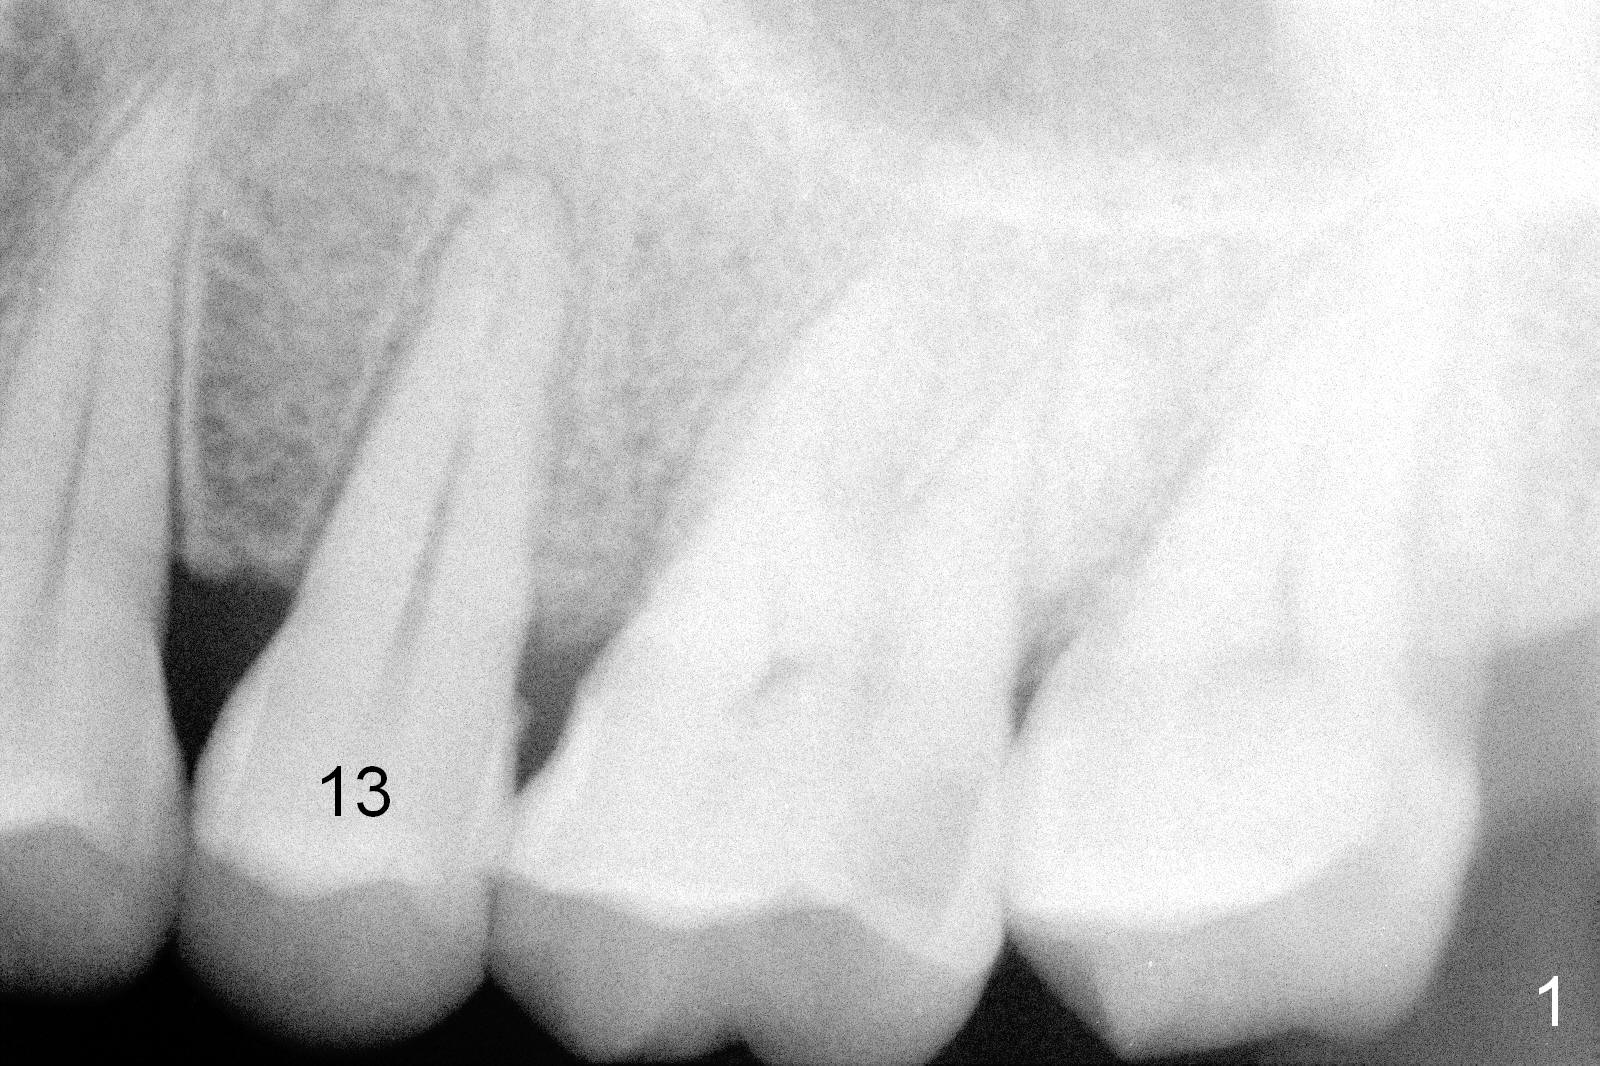

A 47-year-old man returns to clinic with chief complaint "top left tooth chips". Exam reveals subgingival fracture of the lingual cusp of the tooth #13 (Fig.1). A 4.5x17 mm tissue-level implant and 3.5x3 mm abutment appear to be appropriate for the site (Fig.2 (^: sinus floor)). After extraction and socket treatment with 1:50,000 Epinephrine gauze, a 4.5x20 mm tap is placed at the depth of 17 mm. Although the tap has achieved stability, a PA taken with it does not the superior end due to the interference of its long handle (Fig.3 H). A dummy implant (4.5x17 mm) is placed to show its approximation to the sinus floor (Fig.4). After removal of the dummy implant, the definitive implant is placed with certainty with the planned abutment (Fig.5 A). An immediate provisional is placed after bone graft and membrane.